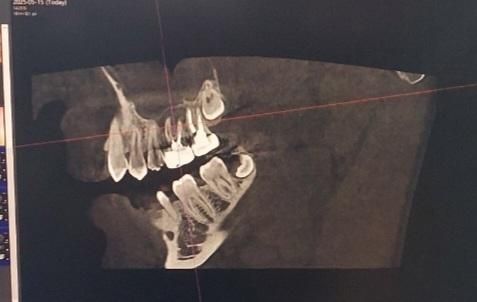

Ct촬영 사진입니다. 첫번째 사진의 경우, 윗니중에 오른쪽에서 3번째 치아가 문제가 되는 금니입니다.(17년전에 치료했던 금니..) 의사분 말씀으로는 해당 금니의 주변잇몸이 거의 녹아서 상악동과 염증이 연결된 형태라고 합니다. 또한 해당 치아의 뿌리는 총 3개인데 이 중 2개의 뿌리주변에 있는 잇몸은 거의다 녹았고, 나머지 1개의 뿌리 주변의 잇몸도 많이 녹았다고합니다. 아마 재신경치료를 해도 성공률이 별로 높지않을거라고 하시던데 저는 최대한 자연치아를 살려서 크라운으로라도 쓰고싶거든요.. 이정도면은 재신경치료로 최대한 자연치아를 살리는 치료가 의미가 없으려나요..ㅠㅠ

ct사진으로 정확히 판독해주시면 감사하겟습니다!

ct상으로 잇몸뼈가 좋진 않습니다. 환자분이 치아를 살려보고 싶다면 재신경치료 치근단 절제술을 해볼수도 잇겟지만 성공률이 낮을것같습니다.

치아뿌리 쪽에 염증의 크기가 큰 것으로 보입니다. 점막 조직이 비후화되어 있는 것이 확인이 됩니다.

1. CT상으로 뿌리 주위 잇몸뼈가 많이 녹았다 -> 맞습니다

2. 그렇게 된 원인이 치아 뿌리 크랙이라면 재신경치료로는 개선되기 어렵습니다, 씹을때 특히 불편하다면 크랙일 확률이 높습니다

3. 그게 아니고 신경치료와 관련된 염증 재발이라면 재신경치료 해볼 수 있습니다.

4. 아니면 정 발치가 싫으시다면 대학병원 보존과 가셔서 치근단 절제술 하세요